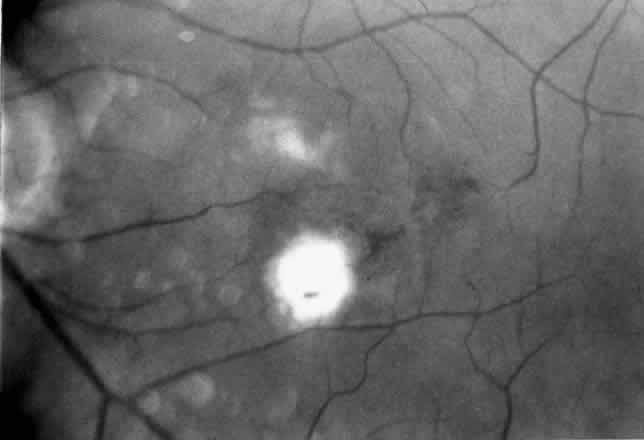

In January 1991, Thomas and Kaplan14 reported an alternative approach to subfoveal neovascularization in POHS. Instead of a large flap retinotomy, their technique employed a small retinal hole through which instruments were introduced into the subretinal space. The neovascular membrane was dislodged, grasped with forceps, and extracted through the slightly enlarged retinotomy. An air-fluid exchange was followed by endolaser burns around the retinotomy and short-term tamponade with sulfur hexafluoride gas. In the first two POHS cases, visual acuity improved dramatically (from 20/400 [6/120] to 20/20 [6/6] in one case and 20/400 [6/120] to 20/40 [6/12] in the second). These early encouraging results prompted refinement of the instrumentation and surgical technique and their application in a wider variety of cases.15

In most cases that meet the criteria for subretinal surgery, the edge of the neovascular complex can be readily visualized under the operating microscope without angiography. In some relatively recent membranes, even if they are anterior to the RPE, we have found the edges to be more difficult to discern. Thus, on occasion, it is helpful to select a frame from the preoperative fluorescein angiogram to project on a screen in the operating room. The image is inverted and reversed to match the surgeon's view through the operating microscope at the top of the patient's head.

Besides being in the most advantageous location, the retinotomy should be as small as possible. Initially, we lightly diathermized the surface of the retina and then used the myringotomy blade to tease open a small hole through which an angled infusion needle was introduced.15 At the suggestion of Lambert and co-workers at Emory University, we stopped using diathermy. We now use a 120° angled, sharply pointed 36-gauge subretinal pick to pierce undiathermized neurosensory retina (Fig. 2). Occasional slight retinal hemorrhage can be controlled by transiently increasing the intraocular pressure. After the tiny hole has been made, the surgeon introduces the angled 33-gauge infusion needle beneath the retina and the assistant gently infuses balanced salt solution to elevate the neurosensory retina. This is accomplished by pushing on the plunger of a syringe that is connected to the hub of the needle by a short piece of tubing. As the fluid enters the subretinal space, attention is directed to edges of laser scars and/or adhesions to the underlying membrane (Fig. 3). Excessive infusion pressure can easily tear the retina. If areas of retina remain adherent, the infusion is stopped and the tip of an angled subretinal pick is carefully passed over the anterior surface of the membrane surface to break any residual adhesions. In a similar manner, the tip of the angled subretinal pick can be used to gently separate the thinned retina from an underlying photocoagulation scar. Occasionally, horizontal subretinal scissors are necessary to cut firm adhesions. These scissors have a similar 130° bend and blades approximately 3 mm in length to allow manipulation through an eccentric retinotomy. Trauma to foveal photoreceptors from either the pick or scissors is carefully avoided. If the retina is not mobilized over the entire photocoagulation scar, separation is achieved at least far enough into the scar to allow manipulation and extraction of the membrane without tearing the adjacent retina. The sharp tip of the angled subretinal pick is used to elevate the edge of the neovascular complex from the underlying RPE (Fig. 4). Care is taken to swing the pick in a pivoting or rotating manner to stretch or enlarge the retinotomy as little as possible. This requires close attention not only to the primary site of action at the membrane but also to the instrument shaft at the retinotomy site. In the appropriate cases, the complex dislodges easily from the underlying subfoveal RPE but remains attached to the edge of a laser scar (in recurrent cases) or to the stalk of choroidal vascular ingrowth.